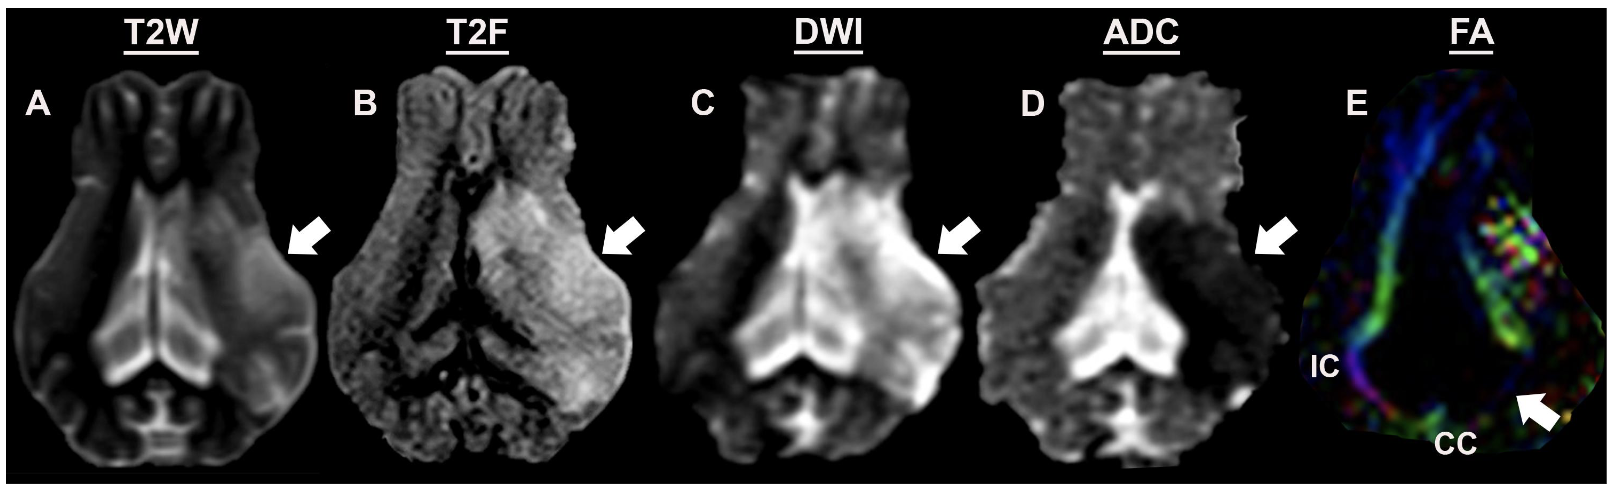

9 types of mri sequences

t1 weighted, t2 weighted, t2 fluid attenuated inversion recovery, diffusion weighted imaging, perfusion weighted imaging, susceptibility weighted imaging, magnetic resonance angiography, diffusion tensor imaging, functional mri

sensitive to water content, useful for detecting fluid and edema, higher resolution than t1w seq

t2 weighted

suppresses signal from cerebral spinal fluid, making it excellent for visualizing subtle changes in brain parenchyma

flair

measures the movement of water molecules, allowing for the detection of tissue damage and ischemia, particularly in the brain

dwi

subsequence of dwi

apparent diffusion coefficient maps

adc maps

quantify mobility of water molecules in tissues

hypointense

restriction of water

hyperintense

flow of water

subsequence of dti

fractional anisotropy maps

fa maps

water diffusivity that reflects white matter properties

red

transverse fibers

green

anteroposterior fibers

blue

craniocaudal fibers

what is this an mri of

ischemic stroke